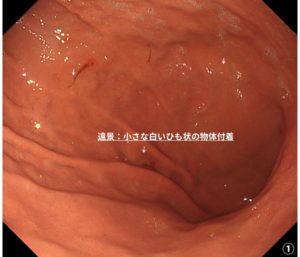

当院の胃内視鏡で見つかった胃アニサキス症